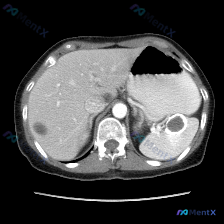

今天整理了一份上腹部增强CT的影像资料,结合临床分析思路,觉得挺有讨论价值的,分享给大家。 影像核心发现 上腹部增强扫描(软组织窗): - 肝脏:轮廓光滑,密度均匀,未见明确局灶性病变; - 脾脏:体积增大,实质内见多发圆形/类圆形低密度灶,边界相对清晰,增强后无强化或强化程度远低于正常脾实质; -...

今天整理了一张很有启发的上腹部CT平扫影像,核心发现是脾脏内的多发类圆形低密度灶,想和大家一起梳理一下鉴别诊断的思路。 --- 先看影像的客观表现 这是一张上腹部横断面CT平扫(软组织窗): - 肝脏:形态大小、实质密度都还好,没看到明确占位,肝门血管也清晰; - 脾脏:是最显眼的地方——多个类圆形...

今天看到一个提问很有意思——直接问“脾脏病变”,但把影像资料和分析理了理,发现这里有个很典型的临床认知陷阱,整理出来和大家讨论。 先把完整客观影像信息放前面(别被提问带偏): --- 一、客观影像所见(腹部CT平扫软组织窗) 1. 图像质量:伪影少,软组织对比度好,满足诊断 2. 关键解剖结构: -...